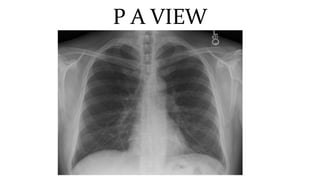

This document discusses key aspects of thorax radiology including positioning for PA and AP views, assessing heart size, visibility of anatomical structures like the scapulae, lungs zones, and measurements like cardiothoracic ratio. It provides guidance on evaluating rotation, inspiration, and penetration on chest x-rays as well as identifying structures like the lobe of azygos vein and aortic knuckle.